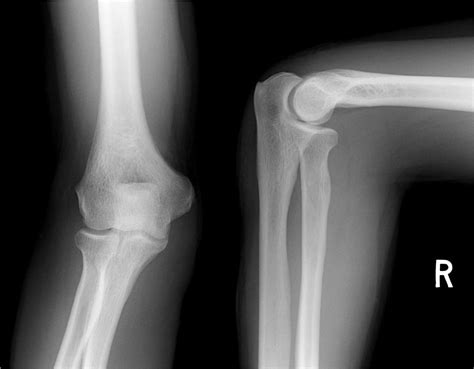

The Anteroposterior (AP) View: A Frontal Look

First up on our X-ray tour is the Anteroposterior (AP) view of the elbow. This is usually the first picture taken, and it gives us a nice, straight-on look at the elbow joint from the front. Imagine you’re looking directly at the palm of your hand – that’s essentially the direction the X-ray beam is traveling: from the front (anterior) through the elbow to the back (posterior). In this view, you’ll see the distal humerus, the proximal radius, and the proximal ulna. The key here is to observe the alignment. The trochlea of the humerus (the spool-shaped part that articulates with the ulna) should align nicely with the trochlear notch of the ulna. Similarly, the capitellum of the humerus (the round knob on the side) should articulate smoothly with the head of the radius. In a normal AP view, you’ll notice clear joint spaces between these bones, indicating healthy cartilage. There shouldn’t be any overlapping of bony structures that suggests displacement, and the overall contour of the bones should be smooth. We’re looking for well-defined edges and no signs of lucency (dark areas) or opacity (bright areas) that aren’t normally present, which could indicate fractures or bone spurs. The olecranon process, that prominent bump at the back of the elbow, will be clearly visible. Pay attention to the relationship between the radial head and the capitellum – they should fit together snugly. If you see any widening of the joint space or misalignment, it might suggest a problem like a ligament injury or dislocation, but in a normal AP view, everything sits just right. This view is fantastic for assessing the overall width of the joint and for spotting fractures in the distal humerus or proximal ulna/radius that might be missed on other views. It’s the baseline, guys, the first step in confirming that everything is structurally sound in your elbow.

The Lateral View: A Side Profile

Next, we move on to the Lateral view of the elbow. This view is absolutely critical because it gives us a profile, a side-on perspective, of the elbow joint. The X-ray beam here travels from the side of the elbow, typically through the pinky-finger side, to the thumb-finger side. This angle is super important for visualizing specific structures and their relationships that the AP view can’t show as clearly. When you look at a normal lateral elbow X-ray, you’ll see the humerus sitting above the ulna and radius. The most telling sign of a normal lateral view is the ‘fat pad’ sign . There are usually small, radiolucent (dark) areas within the joint capsule, representing fat. In a normal elbow, the anterior fat pad is often obscured or very faintly seen, lying along the anterior aspect of the distal humerus. The posterior fat pad, however, normally sits in its groove on the posterior aspect of the humerus and is usually not visible on a standard lateral X-ray. If the posterior fat pad is visible, it often means there’s fluid within the joint, which could be due to a fracture (like a radial head fracture) or other trauma, pushing the fat pad out of its normal position. So, a normal lateral view is one where the posterior fat pad is not seen. Another key landmark is the ‘coronoid line’ . Imagine drawing a line along the anterior border of the coronoid process of the ulna; this line should intersect the capitellum of the humerus in a normal, reduced elbow. Significant displacement or abnormal angulation here can indicate a fracture or dislocation. The olecranon process will also be prominent, and you can assess its relationship with the olecranon fossa of the humerus. The radial head should be clearly visualized articulating with the capitellum. The lateral view is your best friend for spotting elbow dislocations and subtle fractures, especially those involving the radial head or olecranon, because it shows the anterior-posterior relationship of the bones so well. It’s essential for evaluating joint congruity and detecting any subtle swelling or effusion within the joint. Remember, a normal lateral view is clean, showing good alignment and no displaced fat pads.